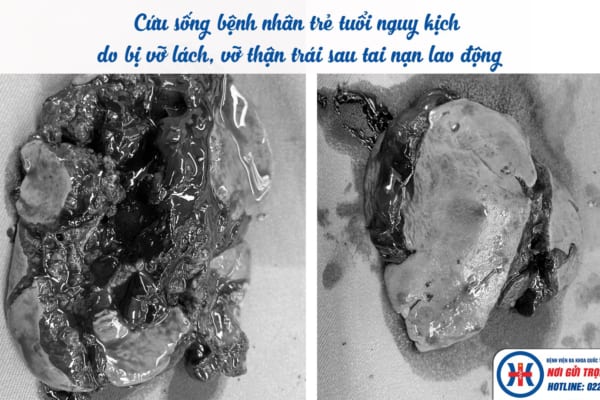

Thực hiện phẫu thuật kịp thời cứu sống bệnh nhân trẻ tuổi đang trong tình trạng nguy kịch do Đa chấn thương sau tai nạn lao động

Sáng ngày 16/5, Bệnh viện đa khoa Quốc tế Hải Phòng – Vĩnh Bảo đã tiếp nhận bệnh nhân Ma Văn H. (35 tuổi) đang trong tình trạng sốc đa chấn thương nguy kịch…